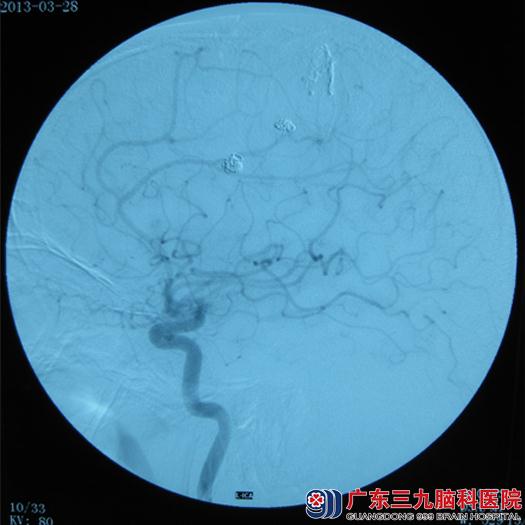

现年32岁的谭某最近在家突发头痛、右侧肢体乏力。到当地医院就诊,CT提示:左侧额顶叶脑出血并破入脑室。对症处理后头痛减轻,右侧肢体肌力好转。家属为求进一步治疗,遂转入广东三九脑科医院神经外七科(血管神经外科)。入院体查合作不理想。神志清楚,双侧瞳孔等大等圆,对光反射灵敏;左侧肌力5级,肌张力正常。右侧肌力3级,肌张力正常;左侧腱反射正常,右侧腱反射减弱,巴氏佂阴性。入院后,MRA、CTA提示动静脉畸形合并动脉瘤。完善术前其他相关检查,并与家属交待病情与风险,家属表示理解并同意介入栓塞手术。于近日行介入治疗。术中见左侧大脑前动脉额内后动脉多发动脉瘤,呈串珠样,囊状,左侧额叶动静脉畸形。外七科吾太华主任分别用弹簧圈填塞动脉瘤、外科胶栓塞动静脉畸形,术程非常顺利,术后给予抗凝血、抗感染、营养支持等治疗。术后经过两周的康复锻炼,右侧肢体肌力恢复正常出院。

血管神经外科主任吾太华介绍道:颅内动脉瘤合并脑动静脉畸形是一类比较特殊的脑血管疾病,在临床工作中较为少见。由于同时存在的动脉瘤与动静脉畸形之间具有复杂的血流动力学关系,故此类患者的临床处理较为棘手。颅内动脉瘤合并动静脉畸形的治疗手段包括手术治疗、血管内栓塞治疗以及放射治疗。本病例,动脉瘤有多个,呈串珠样,载瘤动脉细小,不适合手术治疗,只能选择血管内栓塞治疗。

术前DSA